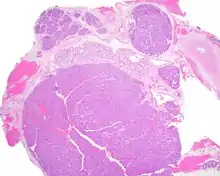

Most patients present in the 7th decade of life, with females affected much more commonly than males (about a 4:1 ratio). The vast majority of the tumors present in the upper lip, although a few present in the palate or buccal (cheek) tissue as a slowly enlarging mass.[3] It is curious that the tumor may show multifocality or multinodularity, a finding that should not be confused with invasion clinically or with malignancy.[1][4]

Tumors are usually small because they come to clinical attention early on in development, with an average size of about 1.6 cm.[1] There is a very characteristic appearance to the tumor when reviewed histologically.

There is a canalicular pattern with cords and ribbons showing connection points between opposing columnar cells within spaces that is called a "string of pearls" appearance.

There are often small luminal squamous balls or morules. There is a very well-developed supporting tissue that is a loose, fibrillar stroma, rich in hyaluronic acid and chondroitin sulphate.[1] In a few cases small calcifications or microliths may be present. Although seldom necessary, a pathologist can do immunohistochemistry studies to confirm the diagnosis, with the cells strongly reactive with pancytokeratin, S100 protein and SOX10, with a delicate GFAP reaction around the periphery.[5][1][6][7] Even though it is a benign tumor, it must be separated from a basal cell adenoma, pleomorphic adenoma, adenoid cystic carcinoma, and polymorphous adenocarcinoma.